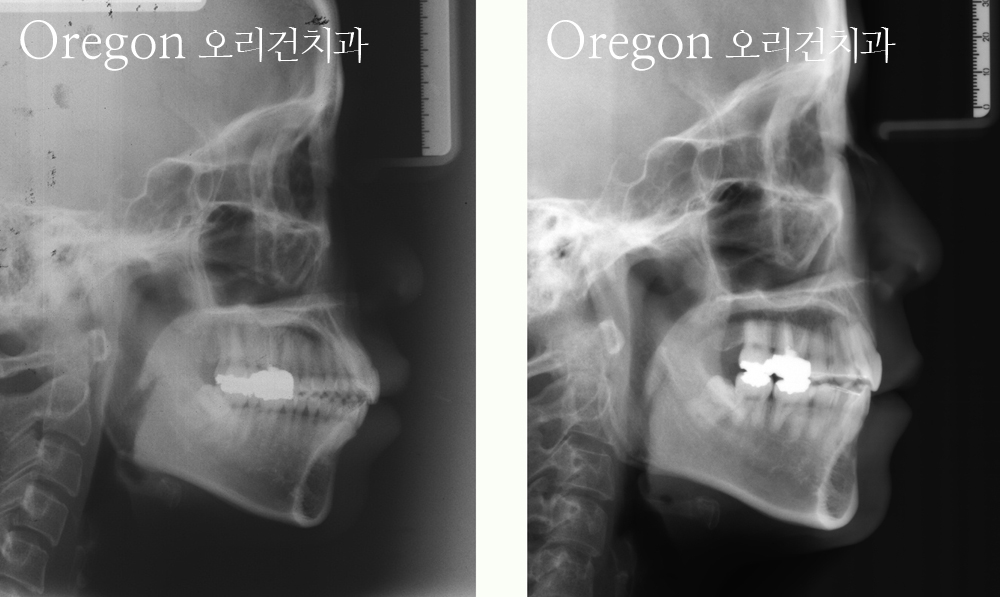

아래 사례는 모두 교정만으로 잇몸돌출이 개선된 사례입니다.